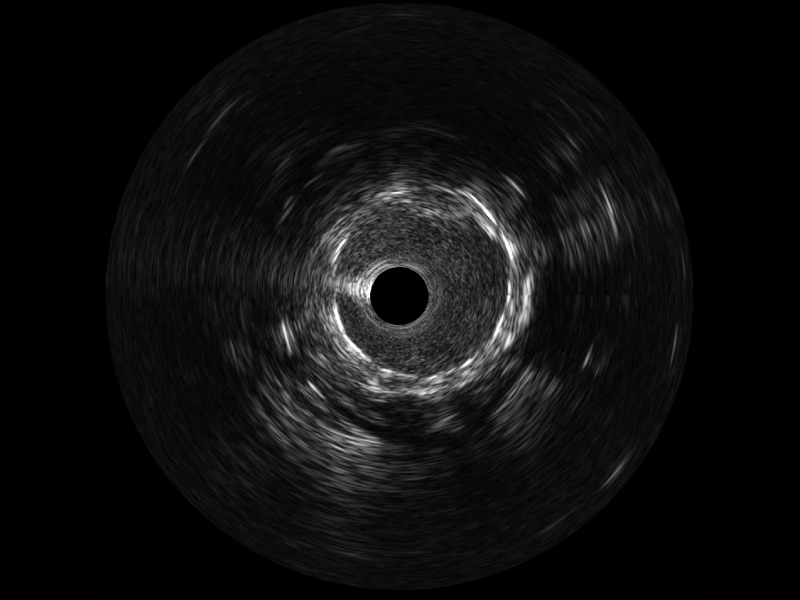

竞技宝(JJB)官方网站宽频IVUS图像

对比传统IVUS导管成像,竞技宝(JJB)官方网站宽频IVUS图像的近场支架梁显影更细腻,远场中膜外血管仍清晰可辨,兼顾远中近,兼顾分辨力与穿透深度